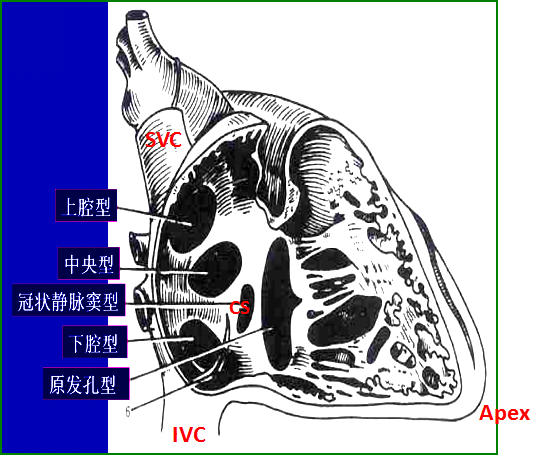

房间隔缺损:病理类型

△ 原发孔型:约占15%

△ 继发孔型:约占75%

△ 静脉窦型:约占5%

△ 冠状静脉窦型:约占2%